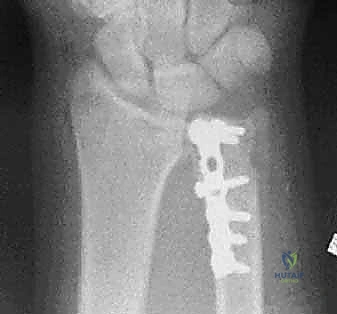

ثانياً: العلاج الجراحي (Surgical Intervention)

متى يقرر الدكتور هطيف ضرورة التدخل الجراحي؟

1. عدم الاستقرار (Instability): إذا كان المفصل الزندي الكعبري البعيد (DRUJ) غير مستقر بعد تثبيت كسر الكعبرة.

2. الانزياح (Displacement): إذا كان الكسر في قاعدة الناتئ الإبري منزاحًا بأكثر من 2 ملم.

3. الكسور المفصلية: أي كسر يخل بتطابق السطح المفصلي لرأس الزند.

4. الكسور المفتتة: في الجزء الكردوسي التي تؤدي إلى قصر عظم الزند.

| مدة التثبيت الأولية | 4 إلى 6 أسابيع من التثبيت الكامل. | بدء الحركة المبكرة (أحيانًا بعد أيام قليلة من الجراحة). |

| المزايا | تجنب مخاطر الجراحة والتخدير، تكلفة أقل. | استعادة التشريح الدقيق، حركة مبكرة، منع تيبس المفاصل، استقرار فوري. |

| التأهيل الوظيفي | يتأخر حتى إزالة الجبس. | يبدأ مبكرًا جدًا مما يعطي نتائج وظيفية أفضل وأسرع. |

خطوات التدخل الجراحي الدقيق مع الأستاذ الدكتور محمد هطيف

تُعد جراحات المعصم والزند من الجراحات الدقيقة التي تتطلب مهارة عالية، وهو المجال الذي يتفوق فيه الأستاذ الدكتور محمد هطيف بفضل استخدامه لتقنيات الجراحة المجهرية (Microsurgery) والأدوات الجراحية ذات التقنية العالية.

يقوم الدكتور هطيف بدراسة الأشعة المقطعية ثلاثية الأبعاد بدقة، ويختار نوع وحجم الصفائح المعدنية (Plates) والمسامير (Screws) المناسبة لكل مريض بناءً على حجم العظم ونوع الكسر.